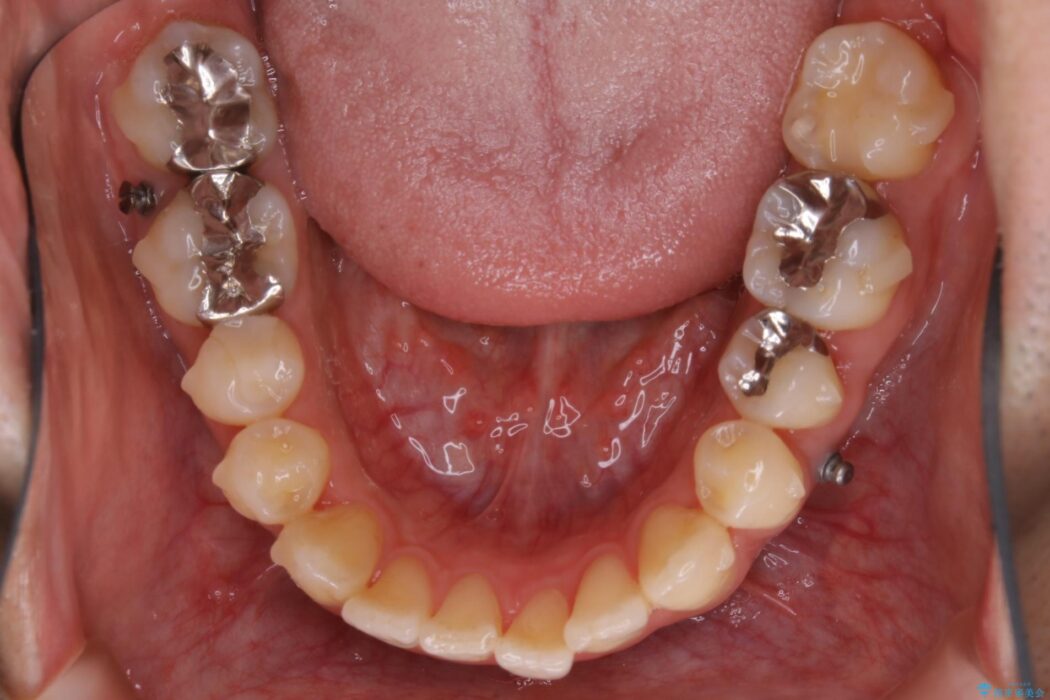

歯列のガタガタと飛び出ている前歯を治したいとのことで来院されました。

装置の範囲内で可能な限り前歯の位置を動かし整えるため、マイクロインプラントを用いて遠心移動をする歯列矯正を計画しました。

本症例では上顎前突(出っ歯)や歯列のがたつきを改善するスペースを確保するために、歯を遠心移動をサポートすることができるマイクロインプラントを用いたゴムかけを行っていただきました。